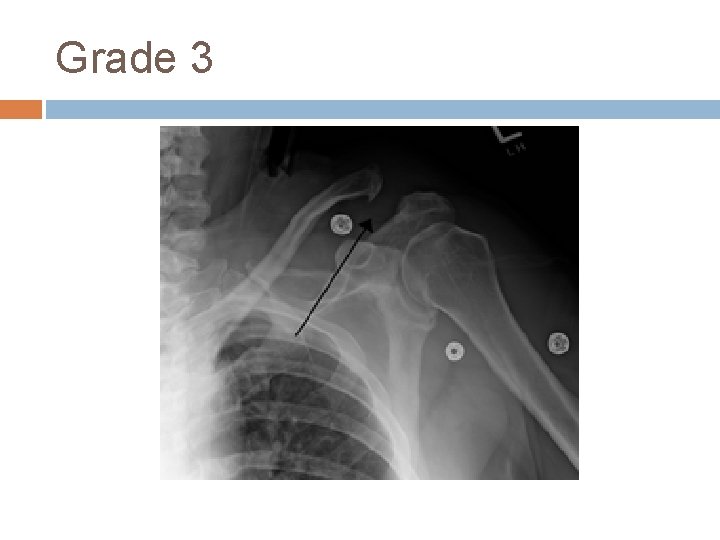

Acromioclavicular Joint AC Sprain/Separation- trauma (acute or repetitive) causing damage/tearing of acromioclavicular and coracoclavicular ligaments Tenderness over AC joint; possibly elevation of clavicle on palpation Classification: -Type I: sprain of AC ligament (CC intact) -Type II: tear of AC (CC intact); slight elevation of clavicle on xray -Type III: complete tear of AC and CC ligs and elevation of clavicle -Types IV-VI: keeps getting worse and damage to surrounding structures

Grade 3

AC Sprain History- fall on shoulder or on outstretched arm (hockey player checked into boards or FB player landing on shoulder; cyclist falling off bike) Exam- cross arm test and O’Brien’s if localizes to AC joint Treatment- sling, ice, analgesics for Type I, II and usually III (sometimes III needs surgery); IV-VI need surgery Recovery- 1 to 6 weeks (or keep playing…)